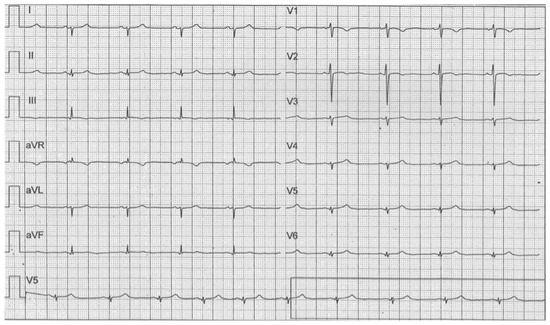

3. Case 2